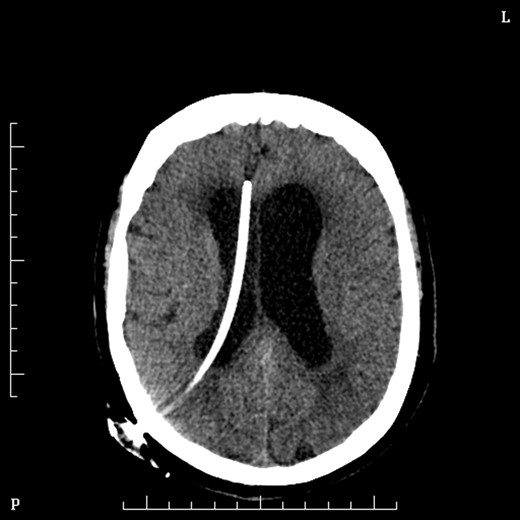

Two days later she underwent an operation to remove the lesion. She was positioned prone in mayfield head clamp and skull pins. A suboccipital craniotomy was performed to gain exposure and the lesion was removed using stereotaxy and operating microscope. Frozen section at the time of surgery was suggestive of Choroid Plexus Papilloma and indeed the formal histopathology confirmed this some days later. Day 1 post-operatively Mrs MM. had cranial nerve VI and VII palsies and was slow to recover. On post-operative day 2 she had a sudden drop on GCS and urgent CT brain demonstrated obstructive hydrocephalus and she underwent insertion of VP shunt (Fig. 4).

On Day 2 post VP shunt insertion, she was noted to be slow to recover and CT abdomen was performed. This demonstrated that the distal catheter tip was not in the pleural space but entered the abdomen and was redirected out along a tract into an umbilical hernia (Fig. 5). The following day she was taken back to theatre and the VP shunt was revised, and good visualization into the abdomen gave the impression that it was correctly in place. Repeat CT abdomen was performed to confirm placement and to our surprise the catheter had re-entered the same tract and travelled into the umbilical hernia (Fig. 6).